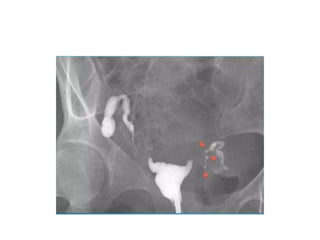

tobacco pouch appearence

• Broad filling defect, smooth regular outline:

polyp/fibroid

• #38 Tobacco pouch appearance, terminal hydrosalpinx with conical narrowing is seen in rt tube,, eversion of fimbria secondary to adhesions..with a patent orifice produces the tobacco pouch appearance in the left terminal